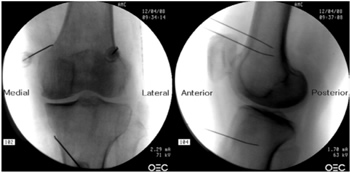

Radiofrecuencia de los nervios geniculados guiados por fluoroscopia

Para realizar una RFTNG guiados por fluoroscopia necesitamos una visión anteroposterior (AP) y lateral de la rodilla (Figura 2). Primero ubicamos al paciente en posición supina con una almohada debajo de la fosa poplítea (para que esté más cómodo) (16). Después de realizar asepsia y antisepsia de la rodilla, procedemos a ubicar los NG (Tabla II). El NGSL se encuentra avanzando la aguja de RFT hacia la confluencia de la diáfisis femoral lateral con el cóndilo femoral lateral en una visión AP y en un punto medio del fémur en una visión lateral. El NGSM se localiza avanzando la aguja hacia la confluencia de la diáfisis femoral medial con el cóndilo femoral medial en una visión AP y en un punto medio del fémur en una visión lateral. Por último, el NGIM se localiza avanzando la aguja hacia la confluencia de la diáfisis tibial medial con el epicóndilo tibial en una visión AP y en un punto medio de la tibia en una visión lateral (16,17).

Fig. 2. Proyección AP y lateral donde se observan las dianas terapéuticas usando fluoroscopia. Imagen tomada del artículo de Choi y cols. (9). Reproducido con la autorización de Jin Woo Shin.

Tabla II. Localización de los nervios geniculados guiados por fluoroscopia

Es muy importante tener una buena visión AP y lateral. En la proyección AP, la articulación tibiofemoral debe tener una anchura similar a ambos lados de la rodilla con el interespacio abierto (9). En la proyección lateral, debe existir una correcta superposición de ambos cóndilos femorales para realizar un bloqueo satisfactorio de los NGSM y NGSL (18).

La mayoría de autores toman las referencias descritas previamente para localizar estos nervios por fluoroscopia, excepto Fonkoué y cols. (18), quienes encuentran que las dianas terapéuticas del NGSM y NGSL (en una visión lateral) se encuentran en la unión del borde superior de sus respectivos cóndilos femorales con la corteza posterior de la diáfisis del fémur, y no en la mitad del espesor del fémur, como se describe clásicamente (9,10,13).